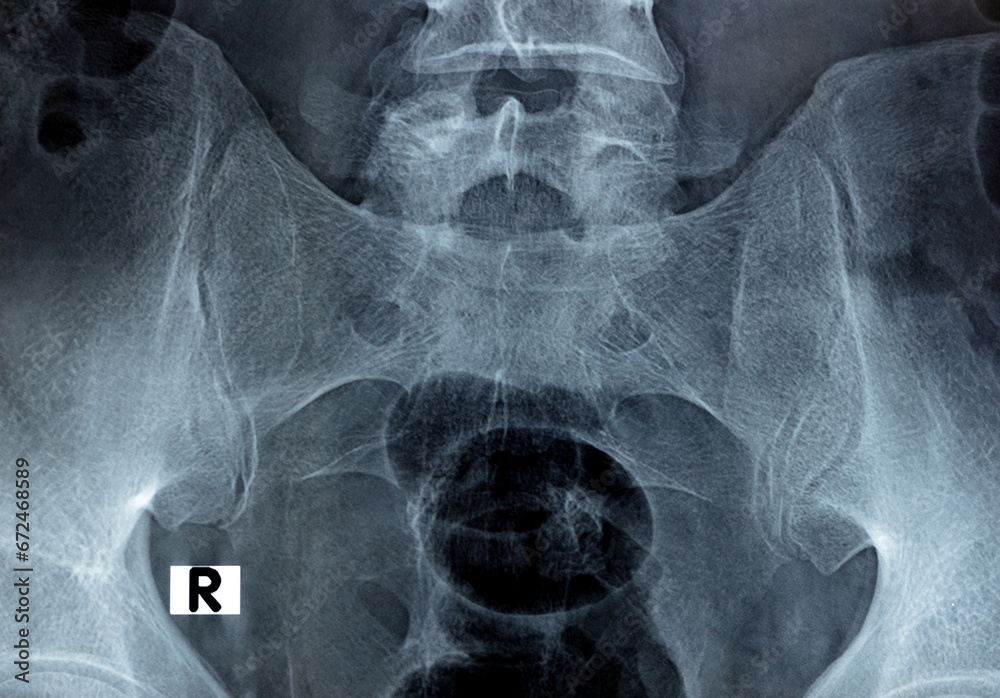

Sacroiliac joint digital radiograph examination Xray reveals preserved Si Joint X Ray View the role of imaging in diagnosing and monitoring rheumatic disorders that affect the sacroiliac joints (sijs) is essential. the sacroiliac joints are composed of two parts, the true joint and a strong retroarticular ligamentous attachment between the two bones (fig 14. The articular surfaces are covered with cartilage and separated by a joint space. specific sacroiliac joint. Si Joint X Ray View.